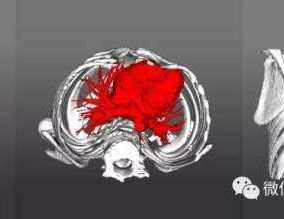

Preoperative Examination

The patient exhibits a noticeable protrusion of the chest wall and a loss of normal spinal curvature, resulting in a visibly unbalanced appearance. He was eventually diagnosed with flatback syndrome combined with a convex deformity of the chest wall.